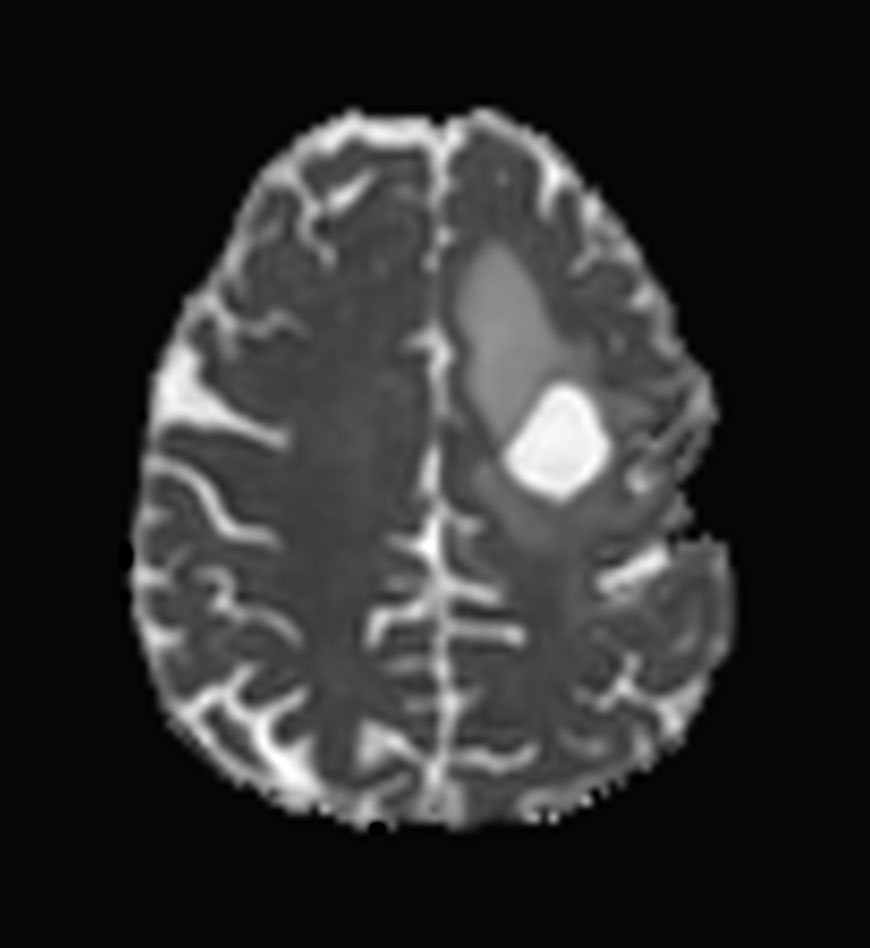

Axial DTI (b1000)

Axial DTI (ADC)